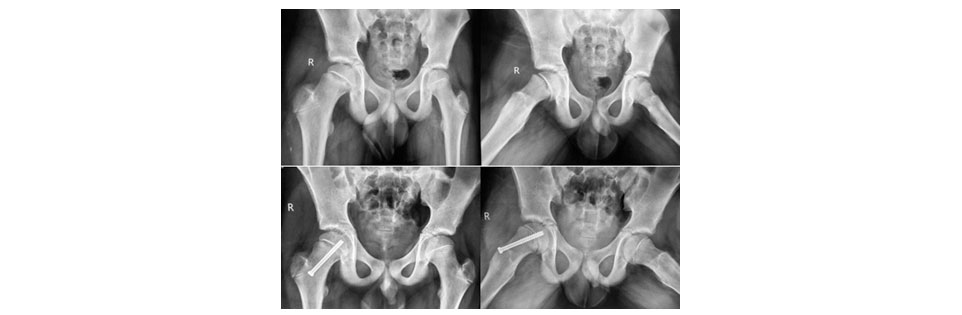

Figure 2: Showing Mild SCFE ® treated with in-situ cannulated cancellous screw fixation.